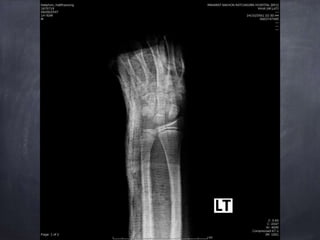

Epiphyseal plate injury Salter harris type 2 Lt.

distal end redius

usually fall on an outstretched hand, extended at wrist

often during sports or play

ชนิดที่ไม่มีการแตกผ่านข้อ ได้แก่ Salter harris type 1 และ 2 ส่วนใหญ่สามารถรักษาได้โดยการทา close

reduction และใส่เฝือก ประมาณ 3-4 สัปดาห์